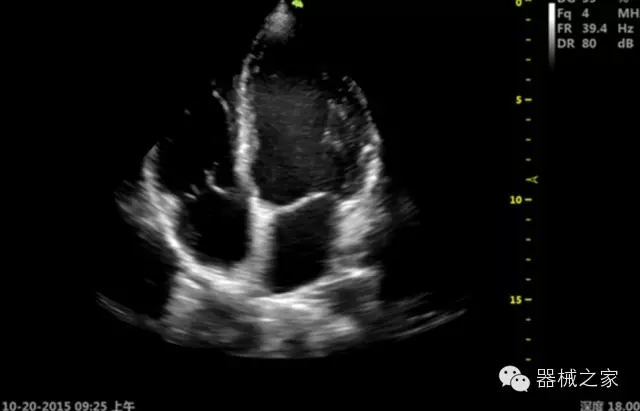

經(jīng)典產(chǎn)品:S8EXP

臨床圖片賞析

產(chǎn)品特點(diǎn)

優(yōu)異的成像技術(shù)

·亞陣元技術(shù):獨(dú)有的亞陣元技術(shù),對(duì)獨(dú)立晶片做二次切割,減少旁瓣偽像,增加臨床診斷的準(zhǔn)確性;

·μ-Scan微米成像技術(shù):開立獨(dú)有的μ-Scan技術(shù),還原出真實(shí)細(xì)膩、層次對(duì)比優(yōu)異的二維圖像;

·倒相諧波成像技術(shù):倒相諧波技術(shù)在去除基波信號(hào)的基礎(chǔ)上獲取兩倍二次諧波信號(hào),提高組織圖像的對(duì)比分辨力;

·智能微血流成像技術(shù):智能微血流捕捉技術(shù)可以提取出隱藏在背景噪聲中的弱血流信號(hào),大大提高低速血流的敏感性;

全面的臨床解決方案

超聲科常規(guī)領(lǐng)域應(yīng)用

·移植S40高端臺(tái)式彩超高端平臺(tái)技術(shù),滿足超聲科腹部、淺表、婦產(chǎn)科、心血管、肌骨等應(yīng)用,提供超聲科完美解決方案;

·實(shí)時(shí)的彈性成像技術(shù):提高了小器管(乳腺,甲狀腺、淺表軟組織腫瘤等)疾病鑒別診斷;

·IMT血管內(nèi)中膜自動(dòng)測量:為血管性疾病評(píng)估提供了有效的評(píng)估手段;

·心功能綜合指數(shù)(TEI指數(shù)):用于左、右心室整體心臟收縮舒張功能評(píng)估的測量方法;

·全方位可調(diào)M型:有利于更好的觀察心腔大小及室壁階段性運(yùn)動(dòng)的異常情況;

·組織多普勒成像(TDI):TDI可定量評(píng)價(jià)心肌運(yùn)動(dòng),判斷是否有局部病變,還可評(píng)價(jià)早期的舒張功能;

·高效3D/4D成像技術(shù):高速的4D幀頻,豐富的3D成像模式,智能斷層切片功能;